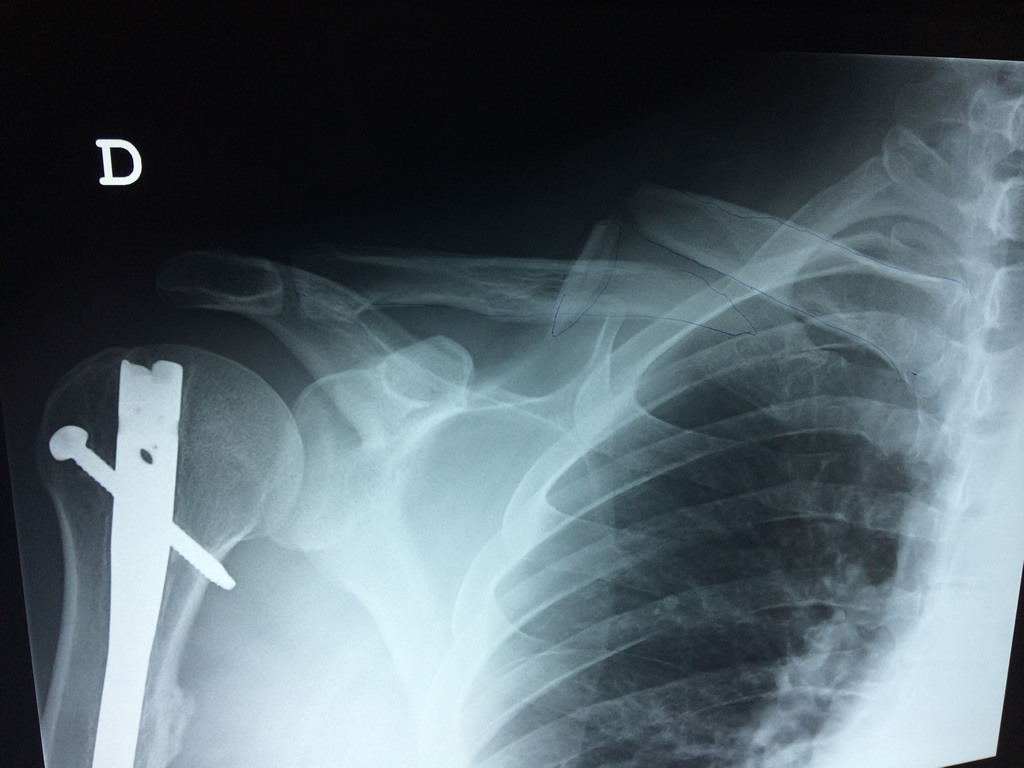

Cirugías de Codos - Clavícula

La clavícula es un hueso largo, con forma de "S" itálica, situado en la parte anterosuperior del tórax. Junto con la escápula forman la cintura escapular. Se puede palpar por toda su longitud y se extiende del esternón al acromion de la escápula, siguiendo una dirección oblicua lateral y posterior.